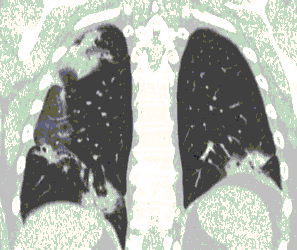

4.3. ЛУЧЕВАЯ ДИАГНОСТИКА COVID-19

Методы лучевой диагностики применяют для выявления COVID-19 пневмоний, их осложнений, дифференциальной диагностики с другими заболеваниями легких, а также для определения степени выраженности и динамики изменений, оценки эффективности проводимой терапии.

КТ имеет высокую чувствительность в выявлении изменений в легких, характерных для COVID-19. Применение КТ целесообразно для первичной оценки состояния ОГК у пациентов с тяжелыми прогрессирующими формами заболевания, а также для дифференциальной диагностики выявленных изменений и оценки динамики процесса. КТ позволяет выявить характерные изменения в легких у пациентов с COVID-19 еще до появления положительных лабораторных тестов на инфекцию с помощью МАНК. В то же время, КТ выявляет изменения легких у значительного числа пациентов с бессимптомной и легкой формами заболевания, которым не требуется госпитализация. Результаты КТ в этих случаях не влияют на тактику лечения и прогноз заболевания при наличии лабораторного подтверждения COVID-19. Поэтому массовое применение КТ для скрининга асимптомных и легких форм болезни не рекомендуется. При первичном обращении пациента с подозрением на COVID-19 рекомендуется назначать КТ только при наличии клинических и инструментальных признаков дыхательной недостаточности (SpO2 < 95%, ЧДД > 22).